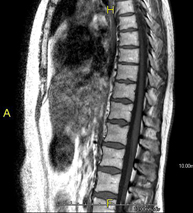

- Thoracic spine MRI

This non-invasive diagnostic procedure uses an electromagnetic field and radio waves (from a transmitter and receiver) to acquire high-definition anatomical images of the thoracic spine. It is a radiation-free procedure. Indicated for: trauma, degenerative problems, hernias, tumours.

- Lumbar spine MRI

This non-invasive diagnostic procedure uses an electromagnetic field and radio waves (from a transmitter and receiver) to acquire high-definition anatomical images of the lumbar and sacral regions. It is a radiation-free procedure. Indicated for: trauma, sciatica, herniated discs, tumours, infections.

- Thoracic + lumbar spine MRI

This non-invasive diagnostic procedure uses an electromagnetic field and radio waves (from a transmitter and receiver) to acquire high-definition anatomical images of the thoracic and lumbar spine. It is a radiation-free procedure. Indicated for: trauma, spinal degeneration, hernias.

A non-invasive diagnostic test that involves obtaining high-definition anatomical images of the thoracic and lumbar spine using an electromagnetic field and radio waves (with transmitter and receiver). It is a radiation-free procedure. Indicated for: trauma, spinal degeneration, hernias.